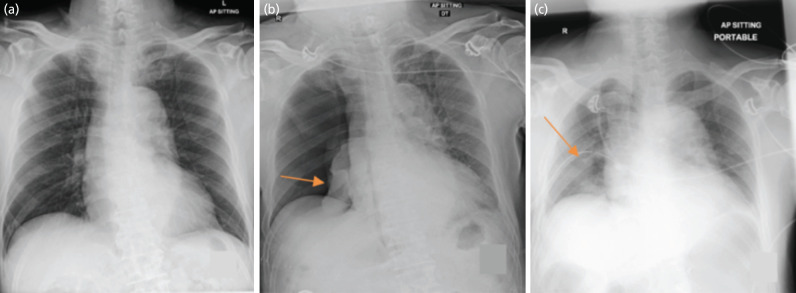

Shoulder arthroscopy is an increasingly common procedure. Pneumothorax post-shoulder arthroscopy is a rare complication. Our aim is to highlight a case report of pneumothorax post-shoulder arthroscopy and to conduct a literature review to evaluate the possible risk factors. We report the case of a 75-year-old male non-smoker, who underwent right shoulder arthroscopy without regional anaesthesia in the left lateral position and subsequently suffered a pneumothorax post-operatively. A PubMed Medline and Cochrane database search was carried out, and 32 articles were identified and thoroughly reviewed. Overall, among the articles that propose a mechanism, 75% (9/12) consider the pathogenesis to be multifactorial. The exact mechanism is currently unknown. Awareness of this complication and timely recognition are important to prevent life-threatening sequelae. Surgeons should maintain a low threshold for obtaining diagnostic plain radiographs in the event of clinical suspicion.